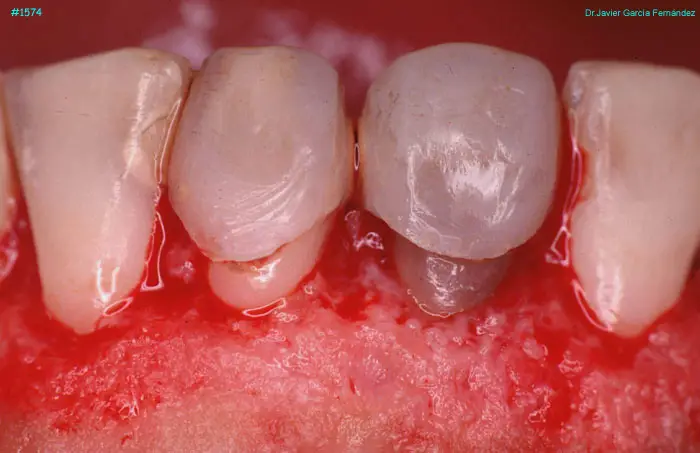

Atlas of Surgical Techniques in Periodontics. Chapter IV. Atlas de Técnicas Quirúrgica en Periodoncia

image 099